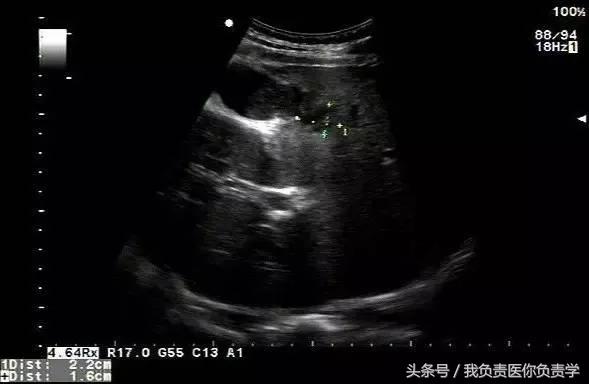

图1示胆囊体积明显增大,内部透声差

图2示胆囊周围可见液性暗区分布

图3-图6示胆囊壁局部回声中断,探头加压及松开时CDFI可见红色及蓝色多普勒信号